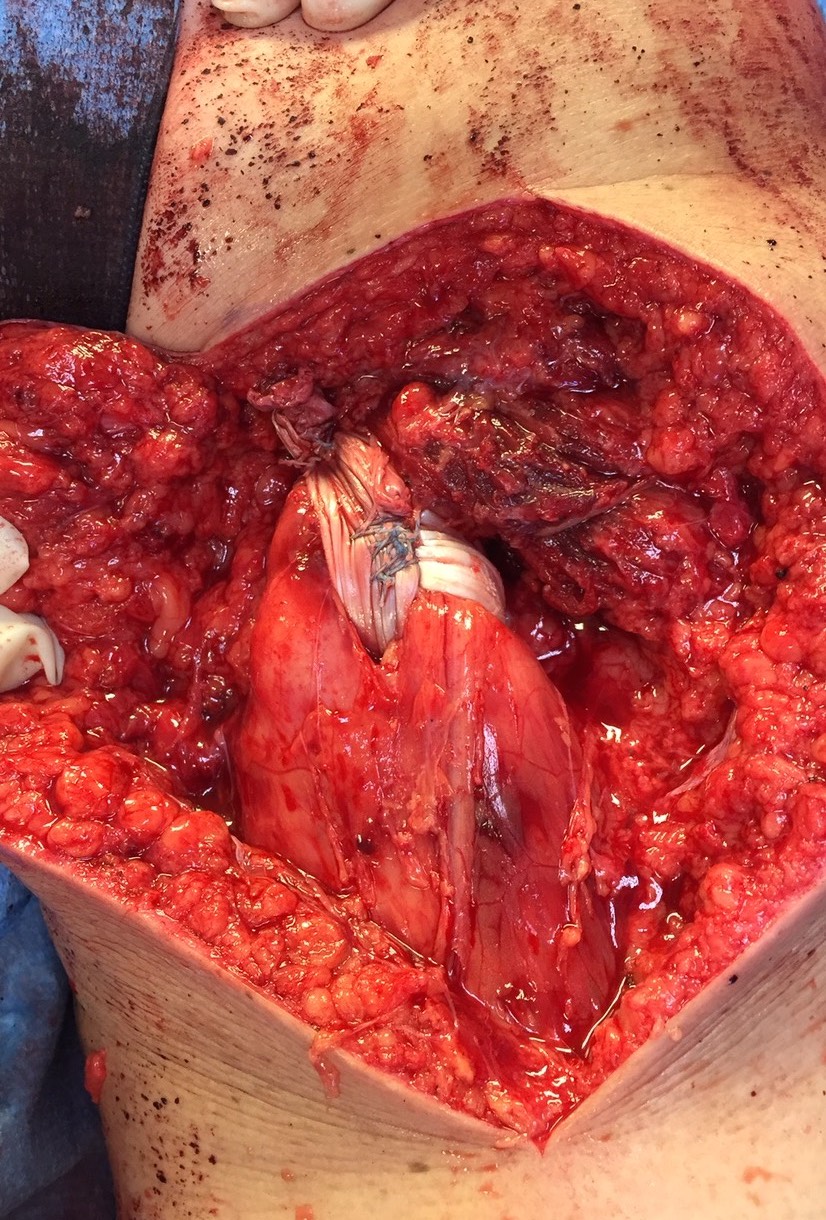

Exposing ischial tuberosity (*) with Cobb retractor

Post suture anchor repair

Ischial tuberosity exposed, then achilles bone block secured with screw

Pulvetaft weave tendon through the strongest, thickest part of the stump